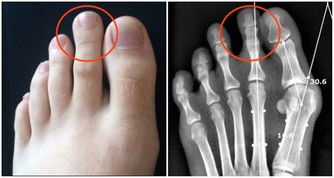

5、走路時有絞痛感當走路或移動時,你的臀部和腿部肌肉有痙攣和絞痛感,稍作休息後有所改善,

可不要以為只是年紀大了或缺乏鍛煉所致,要警惕是外周動脈疾病的信號。

外周動脈疾病,也被稱為PAD。

如果你走路時出現絞痛感,很可能是患了PAD,那麼你的心臟動脈有一半被堵塞的風險。

但也不要太恐慌,PAD是可以治癒的。